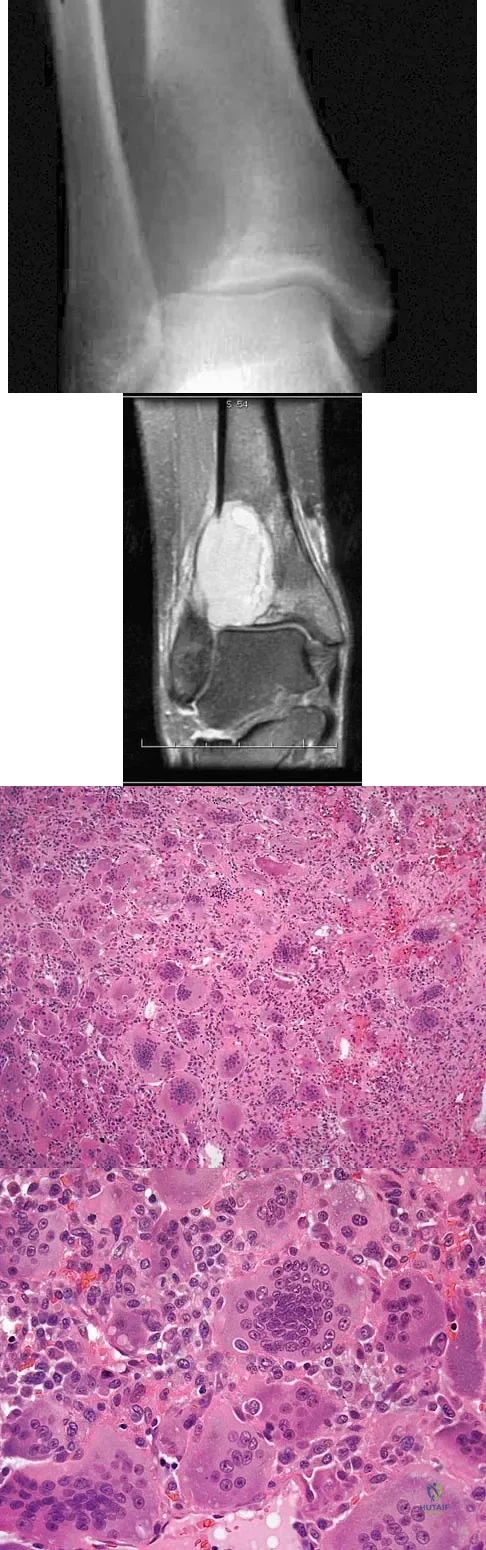

A 19-year-old girl has had pain and swelling in the right ankle for the past 4 months. She denies any history of trauma. Examination reveals a small soft-tissue mass over the anterior aspect of the ankle and slight pain with range of motion of the ankle joint. The examination is otherwise unremarkable. A radiograph and MRI scan are shown in Figures 45a and 45b, and biopsy specimens are shown in Figures 45c and 45d. What is the most likely diagnosis?

Explanation